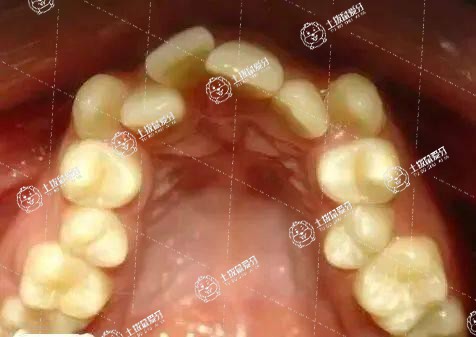

很多時(shí)候,當(dāng)牙友們?nèi)绻霈F(xiàn)牙齒畸形的話,很大程度上是我們交友路上的絆腳石,很多牙友們?cè)诔霈F(xiàn)牙齒畸形的話,往往在微笑或者說話的時(shí)候都變得異常小心翼翼,有的人還會(huì)因?yàn)榛窝例X而給別人留下的印象也不好。在臨床上,牙友們?nèi)绻霈F(xiàn)牙齒擁擠的話,還是需要及時(shí)做矯正牙齒,牙齒擁擠矯正多少錢一次?這或許是牙友們比較關(guān)注的事情,接下來,我們一起來了解一下。

牙齒擁擠需不需要拔牙,這是需要根據(jù)患者的牙齒擁擠的情況來看的。如果牙齒擁擠的程度比較嚴(yán)重,使矯正的位置不夠,則需要進(jìn)行拔牙來留出矯正的空隙。拔牙是為了使牙齒上下左右的協(xié)調(diào)性對(duì)稱,不會(huì)影響到牙齒的美觀、功能和健康。如果是有空隙矯正,則只需要進(jìn)行牙齒矯正就可以。所以,患者的牙齒矯正是否需要拔牙,需要患者到正規(guī)的牙科醫(yī)院進(jìn)行檢查才能來判斷。

牙齒擁擠不拔牙是否可以矯正需根據(jù)具體情況判斷。若患者牙齒擁擠的情況較輕,可以不用拔牙矯正;若患者牙齒擁擠的情況較嚴(yán)重,通常需要拔牙。

在矯正前,醫(yī)生通常會(huì)根據(jù)牙齒拍片檢查、面型、咬合以及需要達(dá)到的矯正效果來判斷是否需要拔牙矯正。若患者牙齒擁擠的程度較輕,可采用擴(kuò)大牙弓的方法排齊前牙,完成矯正,此時(shí)可以不拔牙。但對(duì)于重度牙齒擁擠的患者而言,一般會(huì)采取拔牙的方式,才能保證矯正后的效果。此外,面部前突的患者以及需要矯正咬合關(guān)系的患者通常需要拔牙矯正。如果需要進(jìn)行拔牙矯正但未拔牙的患者,牙齒雖然可以排齊,但矯正效果不穩(wěn)定,容易復(fù)發(fā)。